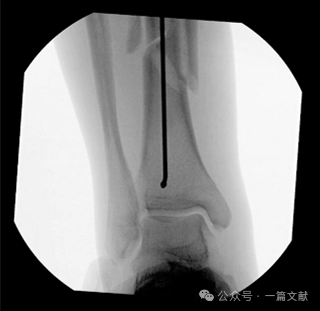

图6,胫骨远端导针的最佳位置:导丝的最佳终点应位于踝穴位,关节面中点稍偏外侧的位置。如下图:

这种方法有助于确保髓内钉的正确位置,避免近端突出。